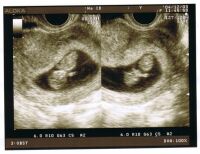

3cmになっていて、普通の大きさだと言われました。なぜか「順調です」とは言わない先生らしい。(^^;でもだいぶ人間っぽく見えてきました。と言っても、まだまだキューピーか?

ちょっとキューピーっぽくなってきた?画面が2分割されているだけで双子ではないです。今日の会計は意外と安くて 2660円でした。毎回このくらいなら良いんですが。。